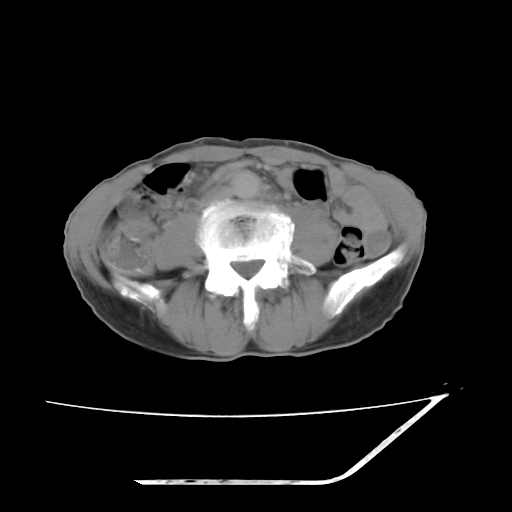

平扫

考虑右肾盂癌,肾动脉受侵,右肾功能减退,右肾盂输尿管积水,管壁增厚,考虑种植转移,应该把下面扫完的

支持右侧肾盂癌伴肾静脉瘤栓形成可能性大,右肾结石.肝右叶后段低密度影,不除外转移.

右肾盂旁ca并肾静脉瘤栓形成/肾功能降低。

右肾结石。

右肾盂癌,肾动脉受侵,右肾盂输尿管积水,管壁增厚,考虑种植转移

右肾盂移行细胞癌并右输尿管中段转移.肾积水.

支持 右侧肾盂癌伴肾静脉瘤栓形成可能性大,右肾结石;肝右叶后段低密度影,不除外转移。

1.右侧肾盂癌伴肾盂积水。

2.肾脏功能减退,原因有:(1)肾动脉受侵。(2)肾静脉受侵(3)肾积水,等。本例,肾动脉显影较好,但受压明显;肾静脉无明显显示,受压或静脉癌栓,下腔静脉腔内未见明显充盈缺损。

3.右侧上段输尿管扩张,原因:(1)积水所致;(2)种植。